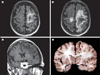

The first part of this review ended with a discussion of new niches for known viruses as illustrated by viral central nervous system (CNS) disease associated with organ transplant and the syndrome of human herpesvirus 6-associated posttransplant acute limbic encephalitis. In this part, we begin with a continuation of this theme, reviewing the association of JC virus-associated progressive multifocal leukoencephalopathy (PML) with novel immunomodulatory agents. This part then continues with emerging viral infections associated with importation of infected animals (monkeypox virus), then spread of vectors and enhanced vector competence (chikungunya virus [CHIK]), and novel viruses causing CNS infections including Nipah and Hendra viruses and bat lyssaviruses (BLV).